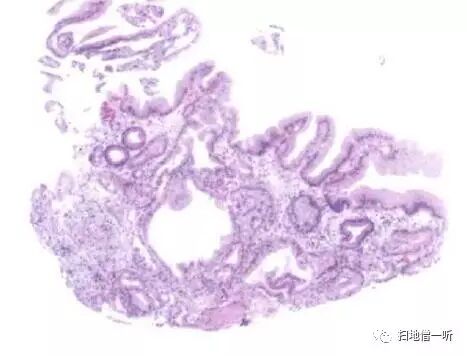

病理组织学可见腺窝上皮增生性变化,腺管囊状扩张